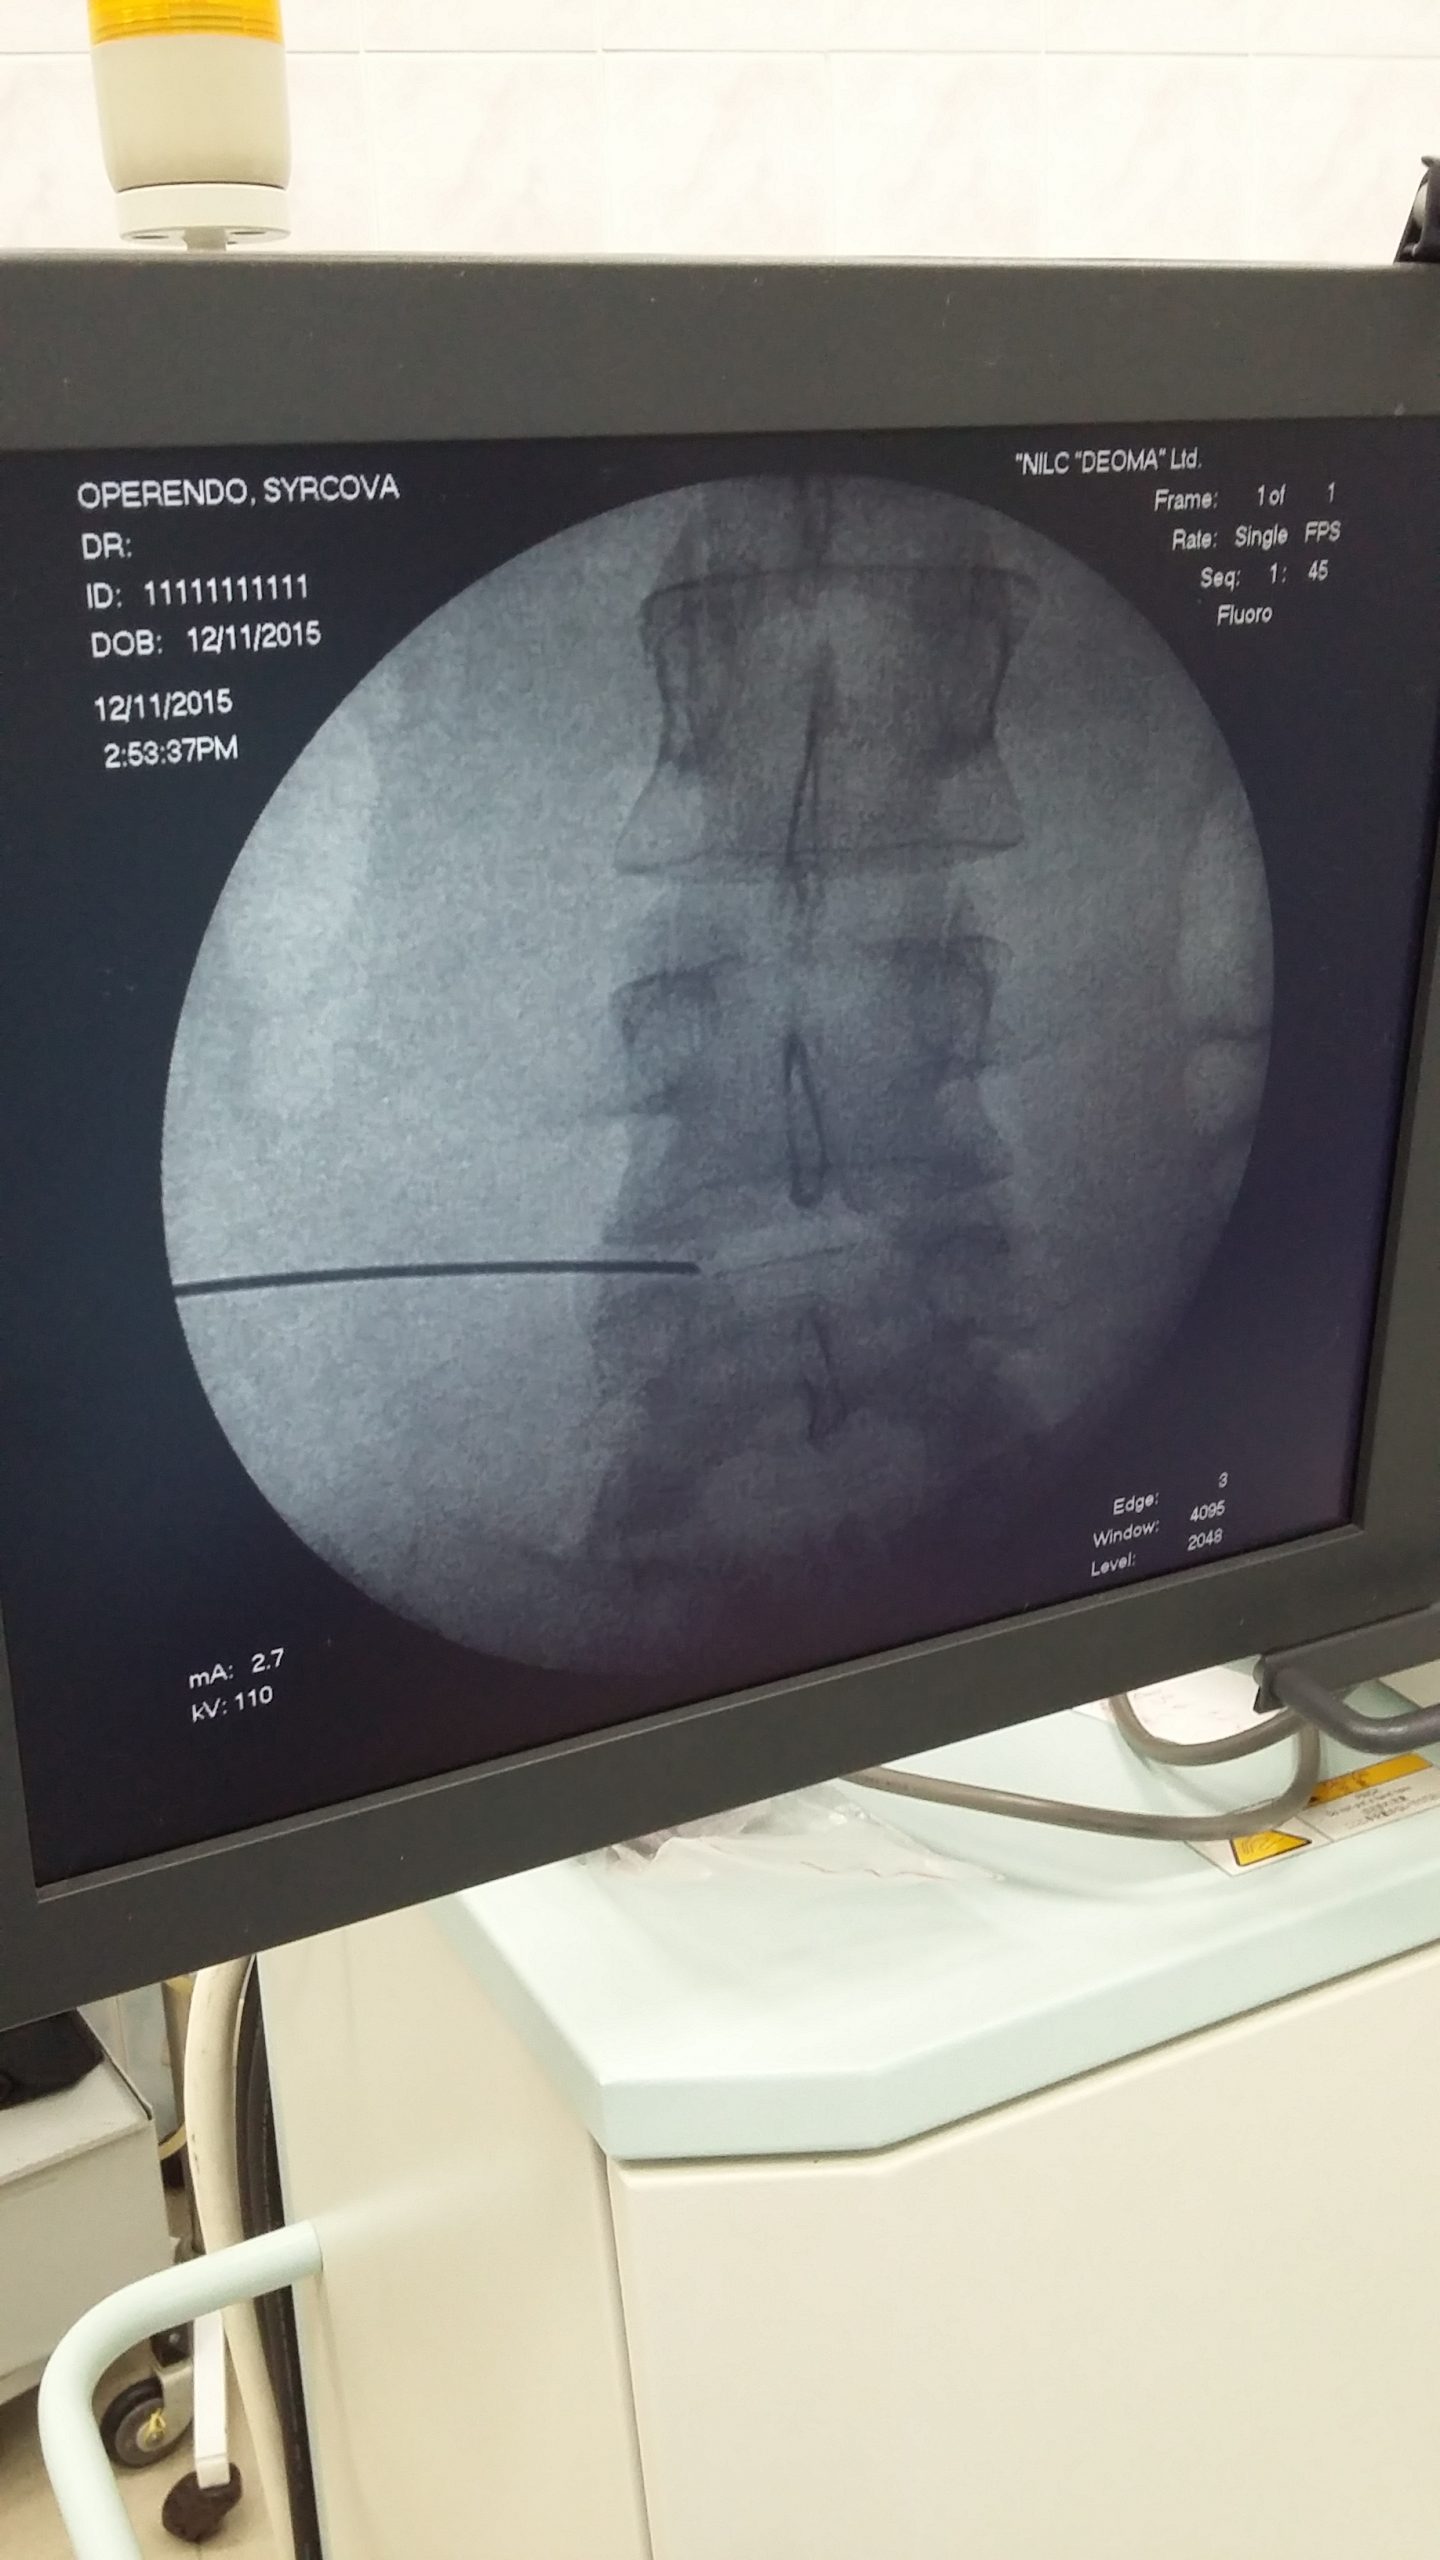

Удаление межпозвоночной больницы 29 фотографий